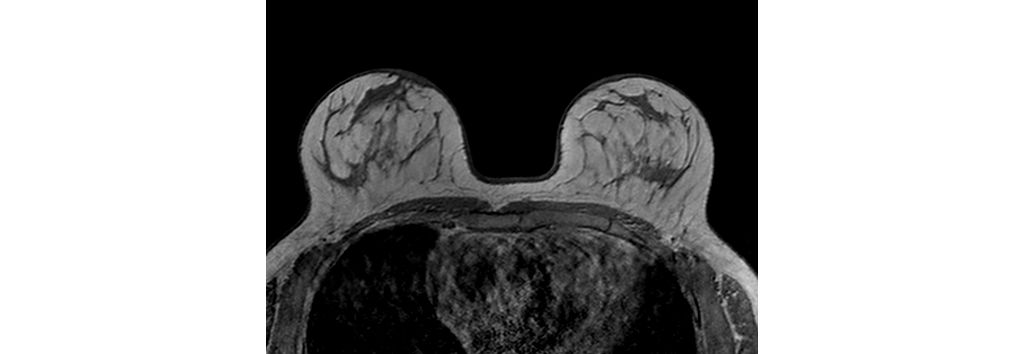

Philips - dStream Breast 7ch coil MR coil - Philips